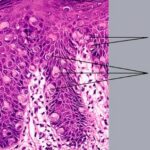

PATHOLOGY The intraepidermal adenocarcinoma of EMPD and MPD has a similar histologic appearance. There are groups, clusters, or single cells within the epidermis that show nuclear enlargement with atypia, prominent nucleoli, and well-defined ample cytoplasms . Intercellular bridges are absent. The cells can be within all levels of the epidermis and can compress but preserve the basal layer without junctional nest formation. The cells can extend into the contiguous epithelium of hair follicles and sweat gland ducts. Acanthosis, hyperkeratosis, and parakeratosis are often present. These cells have a “pagetoid” appearance and simulate other intraepidermal malignancies, including melanoma, pagetoid squamous cell carcinoma in situ, mycosis fungoides, cutaneous adnexal carcinomas (sebaceous carcinoma, porocarcinoma, and others), Merkel cell carcinoma, Langerhans cell histiocytosis, and other epidermotropic cutaneous metastases. The cells of MPD and EMPD can be pigmented, which should not necessarily indicate they are melanocytic. Paget's cells have intracellular mucopolysaccharides, with EMPD having a greater amount of mucin as compared